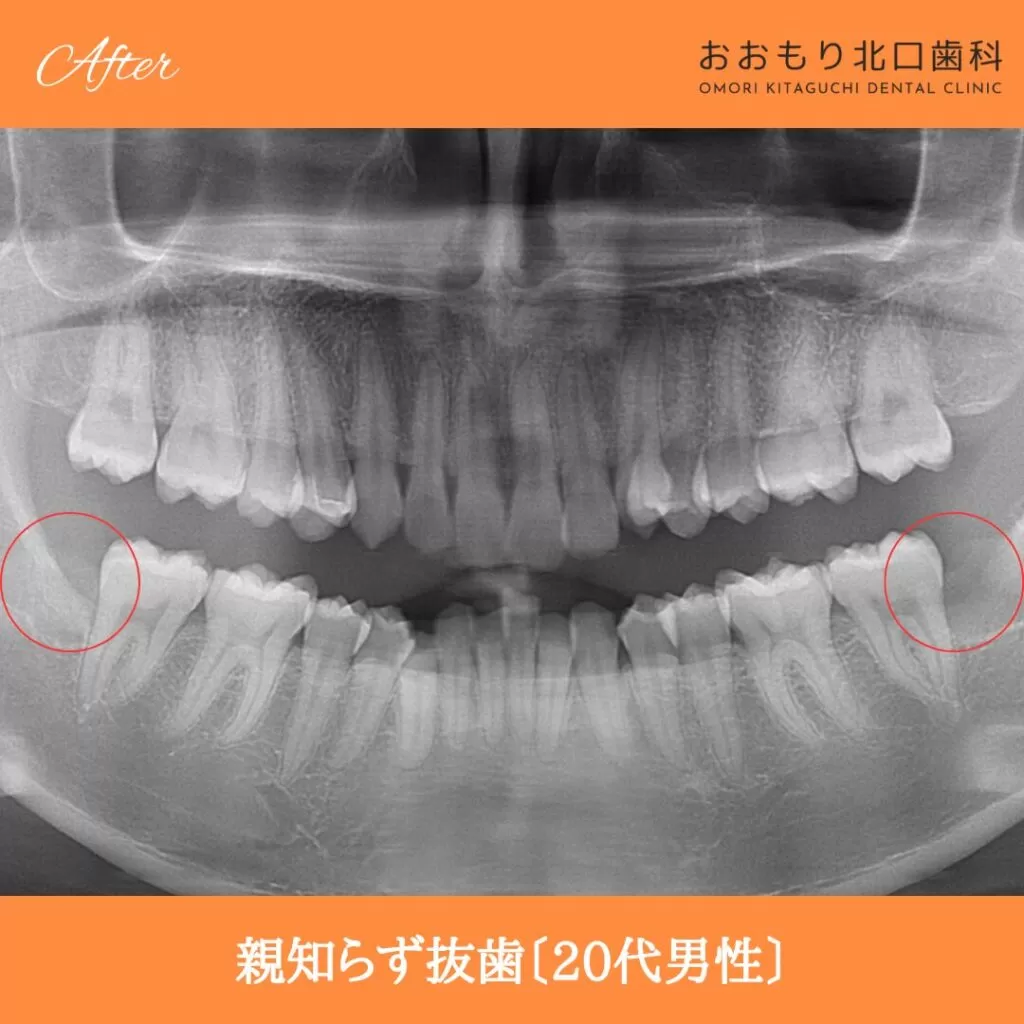

症例紹介㊺親知らず抜歯(20代男性)

本日は「親知らず抜歯」を行われた患者さまのビフォーアフターをご紹介します。

【治療名】親知らず抜歯

【患者さん】20代男性

【費用(税込)】保険治療

【リスク】 親知らずの抜歯は、手術中は麻酔により痛みを感じることがほとんどありません。

しかし、麻酔が切れた後には、時には腫れや痛みが発生することがあります。